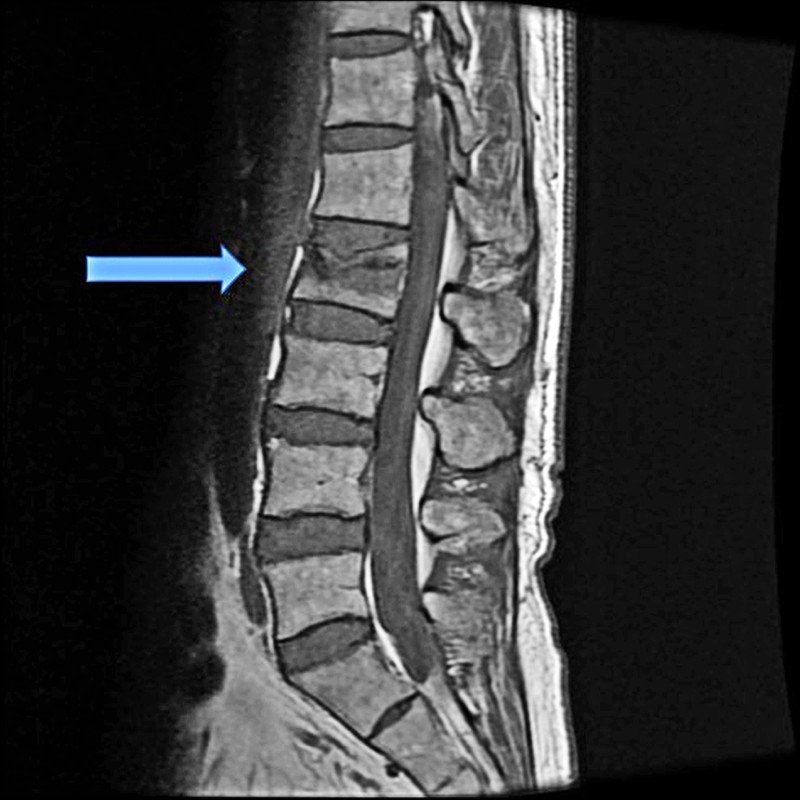

長期缺鈣會造成骨質流失,導致骨質疏鬆,使骨骼變脆、易骨折,這在老年人身上尤其常見。兒童則可能出現骨骼發育異常,如O型腿。牙齒與指甲也可能因缺鈣而變得脆弱、易蛀牙或易斷裂。

此外,背部、腰部或腿部的慢性骨骼疼痛,也可能與骨質減少有關。